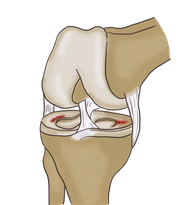

무릎 연골 손상 증상에 대해 자세히 알아보도록 하겠습니다.무릎 연골은 무릎 관절의 부드러운 조직으로, 무릎 관절을 보호하고 스트레스를 흡수하는 역할을 합니다. 연골은 대부분 물과 콜라겐 섬유로 이루어져 있으며, 신체 내부의 혈관이나 신경이 없기 때문에 손상된 경우 치료가 어려울 수 있습니다. 연령이 들면서 연골의 수명이 줄어들 수 있고, 부상이나 연골의 낭비에 따라 연골이 파손되거나 마모될 수 있습니다. 이러한 상황에서는 통증, 불안정감 및 관절 운동 제한 등의 증상이 발생할 수 있습니다. 적절한 치료를 받지 않으면 무릎 관절염과 같은 더 큰 문제가 발생할 수 있으므로, 초기에 진단하고 적절한 치료 계획을 수립하는 것이 중요합니다.

무릎 연골 정보